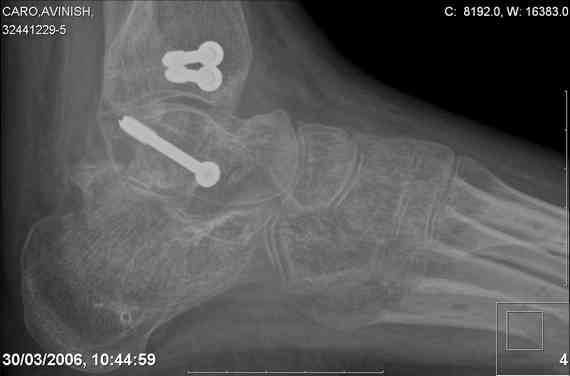

Re: Осколчатый перелом таранной кости

ya by popytalsya sobrat talus anatomichno,seichas pozdno operirovat iz za oteka,po etomy distrakziya apparatom budet optmalna.Posyalu vam podobyai moi sluchai.

14 years old girl

Fall from height ( 3rd floor)